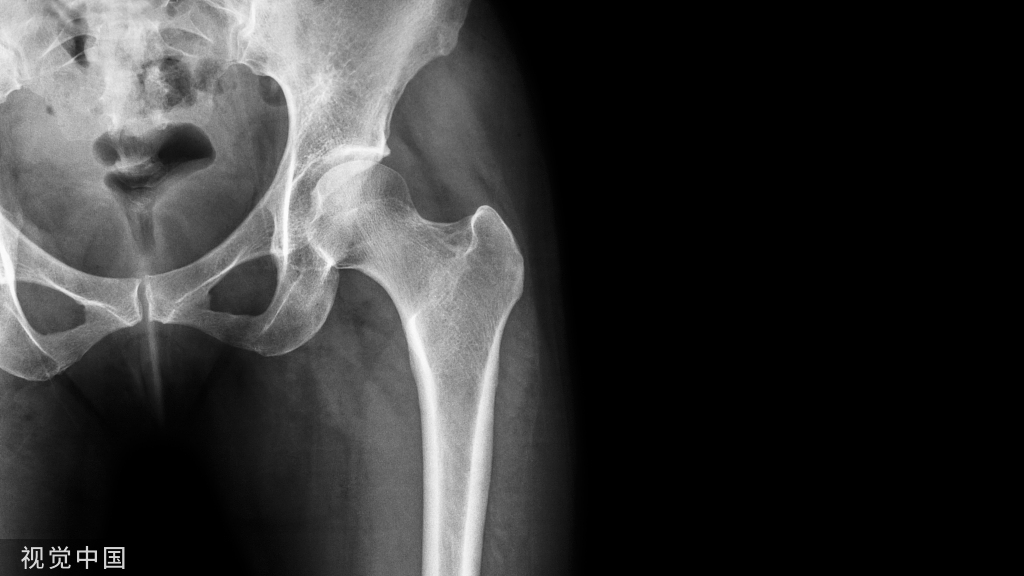

20世纪80年代末至90年代,关于不同种类的内固定装置的实验研究将锁定钢板引入了骨折治疗之中。发展出这种牢固固定方式的初衷是为避免广泛的软组织剥离。主要应用与四肢骨折:

• 干骺端/关节内骨折

• 粉碎性骨折

• 骨质疏松性骨折

• 假体周围骨折